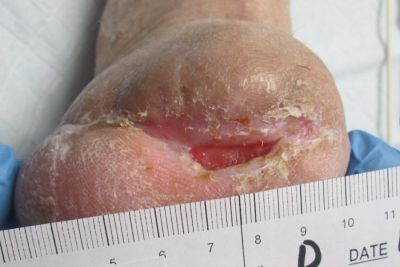

Assessment during her first visit to the clinic revealed trophic skin changes of chronic ischemia, and non-palpable dorsal pedis (DP) or posterior tibial (PT) pulses. Capillary refill was sluggish. The contralateral limb presented similarly. The periwound was boggy and mottled, and the wound bed was a dry, dull red. Bone from the first metatarsal was visible, but appeared viable. Both bone and tissue specimens were taken for PCR (polymerase chain reaction) plus culture and sensitivity, of which only the tissue revealed significant growth of pathogens; osteomyelitis was not suspected at this juncture. The patient's wound was covered with a moisture retentive dressing and she was immediately referred to the lower extremity vascular specialist at the neighboring heart institute, where she underwent successful, albeit complex, vascular intervention.

Within an 8 week period, she received targeted oral antimicrobial therapy and conservative wound care inclusive of sharp debridement, strict offloading, and dressings to promote moisture and healthy tissue proliferation in the wound bed. The patient-centered plan also included glucose control, dietary modification to include protein supplementation, and smoking cessation. Despite all the above measures, the wound continued to probe to bone, and showed little signs of healing.